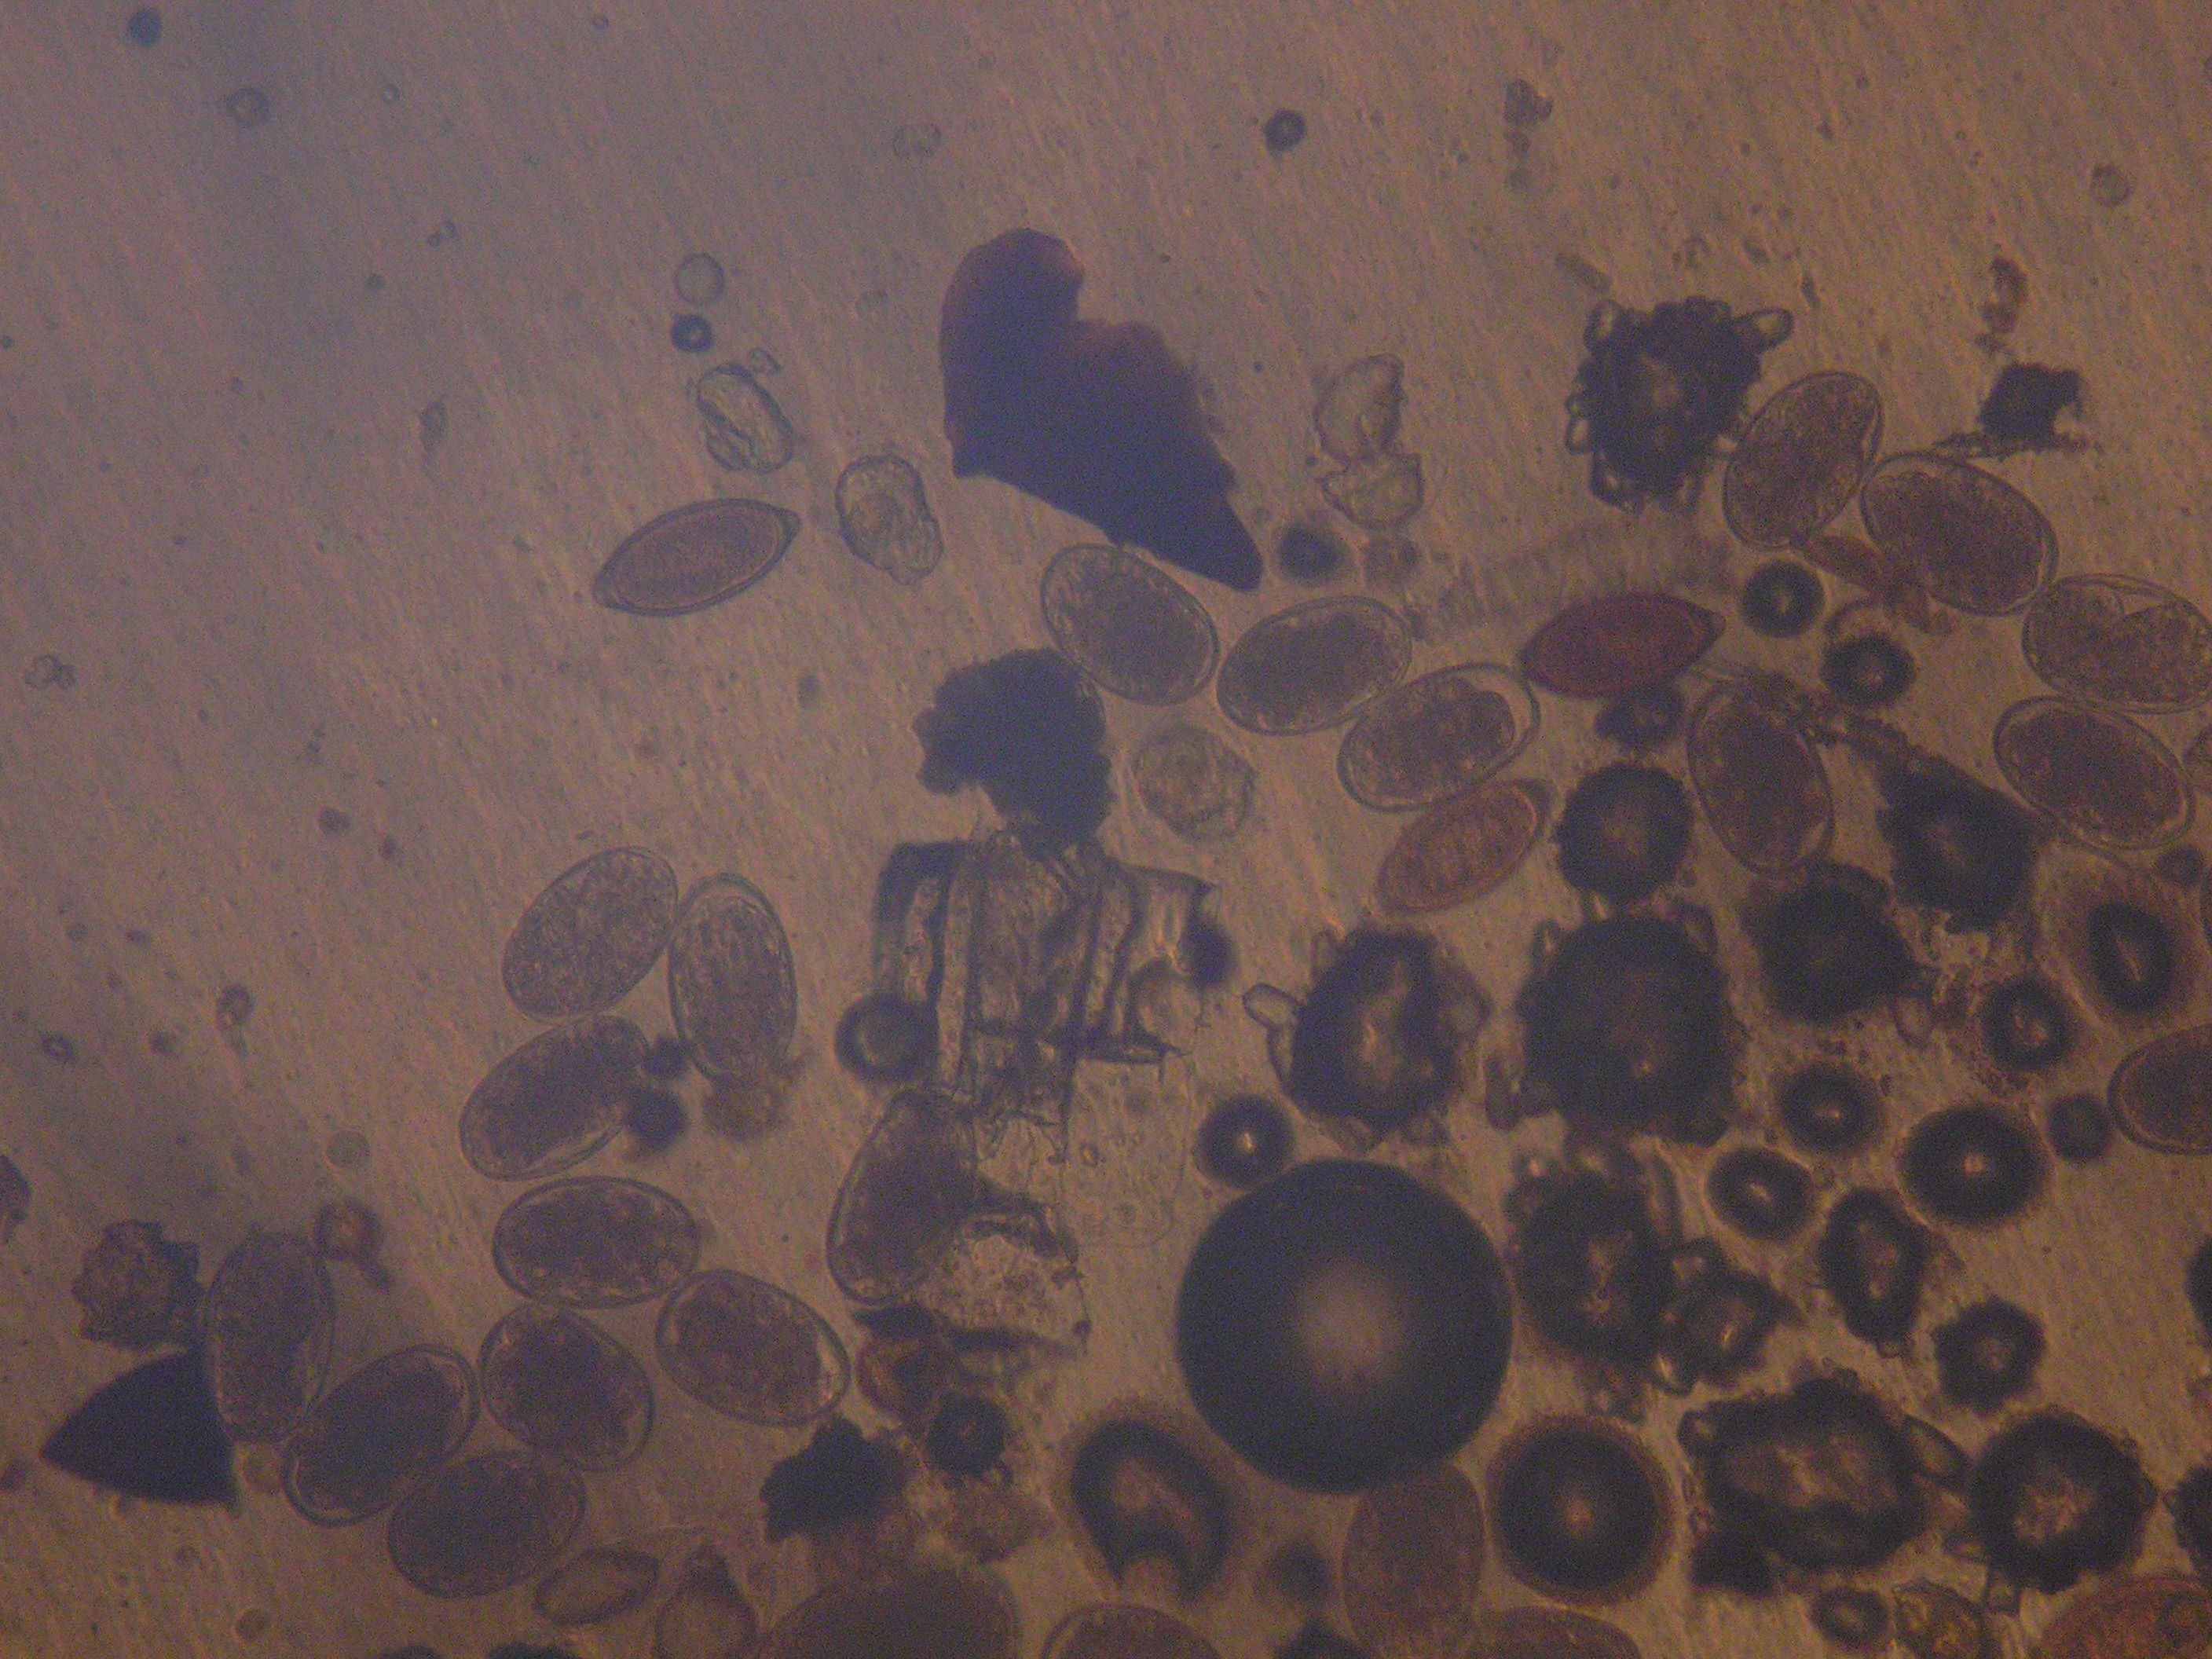

Таким чином, при дослідженні фекалій 65 собак різного віку, відловлених у різних районах м. Харкова, у 39 (60%) встановили 4 види гельмінтів: Uncinaria stenocephala, Toxocara canis, Trichuris vulpis (Trichocephalus vulpis), Dipilidium caninum (Рис. 1-10).

Інтенсивність інвазії, за результатами підрахунку кількості яєць у полі зору становила від 1-3 до 200 (Рис. 1, 2, 5-8 ).

Рис. 1. Яйця унцинарій (А) і токсокар (Б).

Рис. 2. Яйця унцинарій.

Рис. 5. Яйця токсокар (А), яйця унцинарій (Б).

Рис. 6. Яйця токсокар.

Рис. 7. Яйця токсокар (А); унцинарій (Б); утворення личинки в яйці унцинарій (В); неспорульована ооциста ізоспорин (Г); спорульована ооциста ізоспорин (Д).

Рис. 8. Яйця трихурисів (А) та унцинарій (Б).

Рис. 11. Яйця трихурисів (А) і токсокар (Б), кліщі роду Demodex (В).